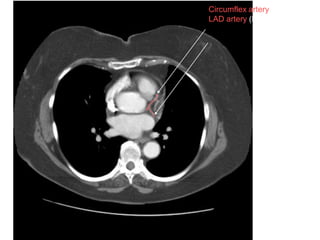

A

D

Circumflex artery (LCx)

LAD artery (LAD)

left ventricular wall and septum

papillary wall muscles

mitral valve leaflets. )

Pericardial sac